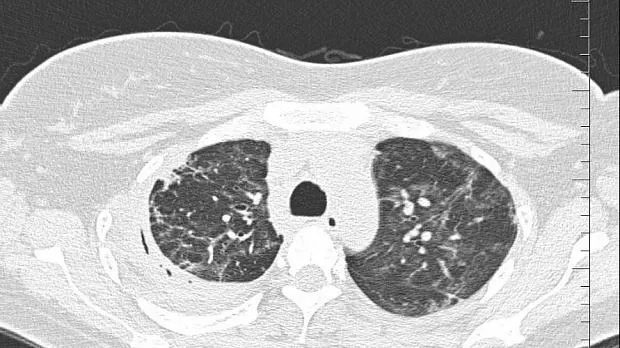

08.06.2020 проведена повторная установка блокатора в промежуточный бронх (блокатор Medlung №13) с хорошим клиническим эффектом (сброс воздуха по плевральному дренажу прекратился через 8 часов после вмешательства). Подтверждено данными Р-КТ органов грудной клетки.